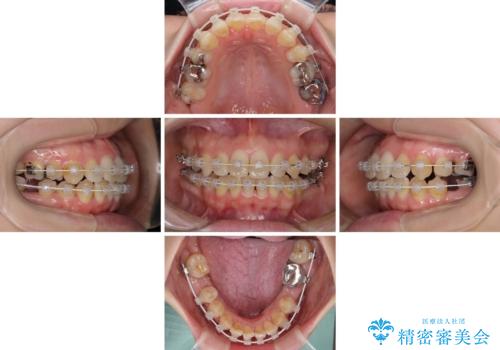

- 審美装置

イレギュラーな大臼歯抜歯矯正であったため、治療期間の長期化が想定されましたが、何とか3年ちょうどで終えることができました。